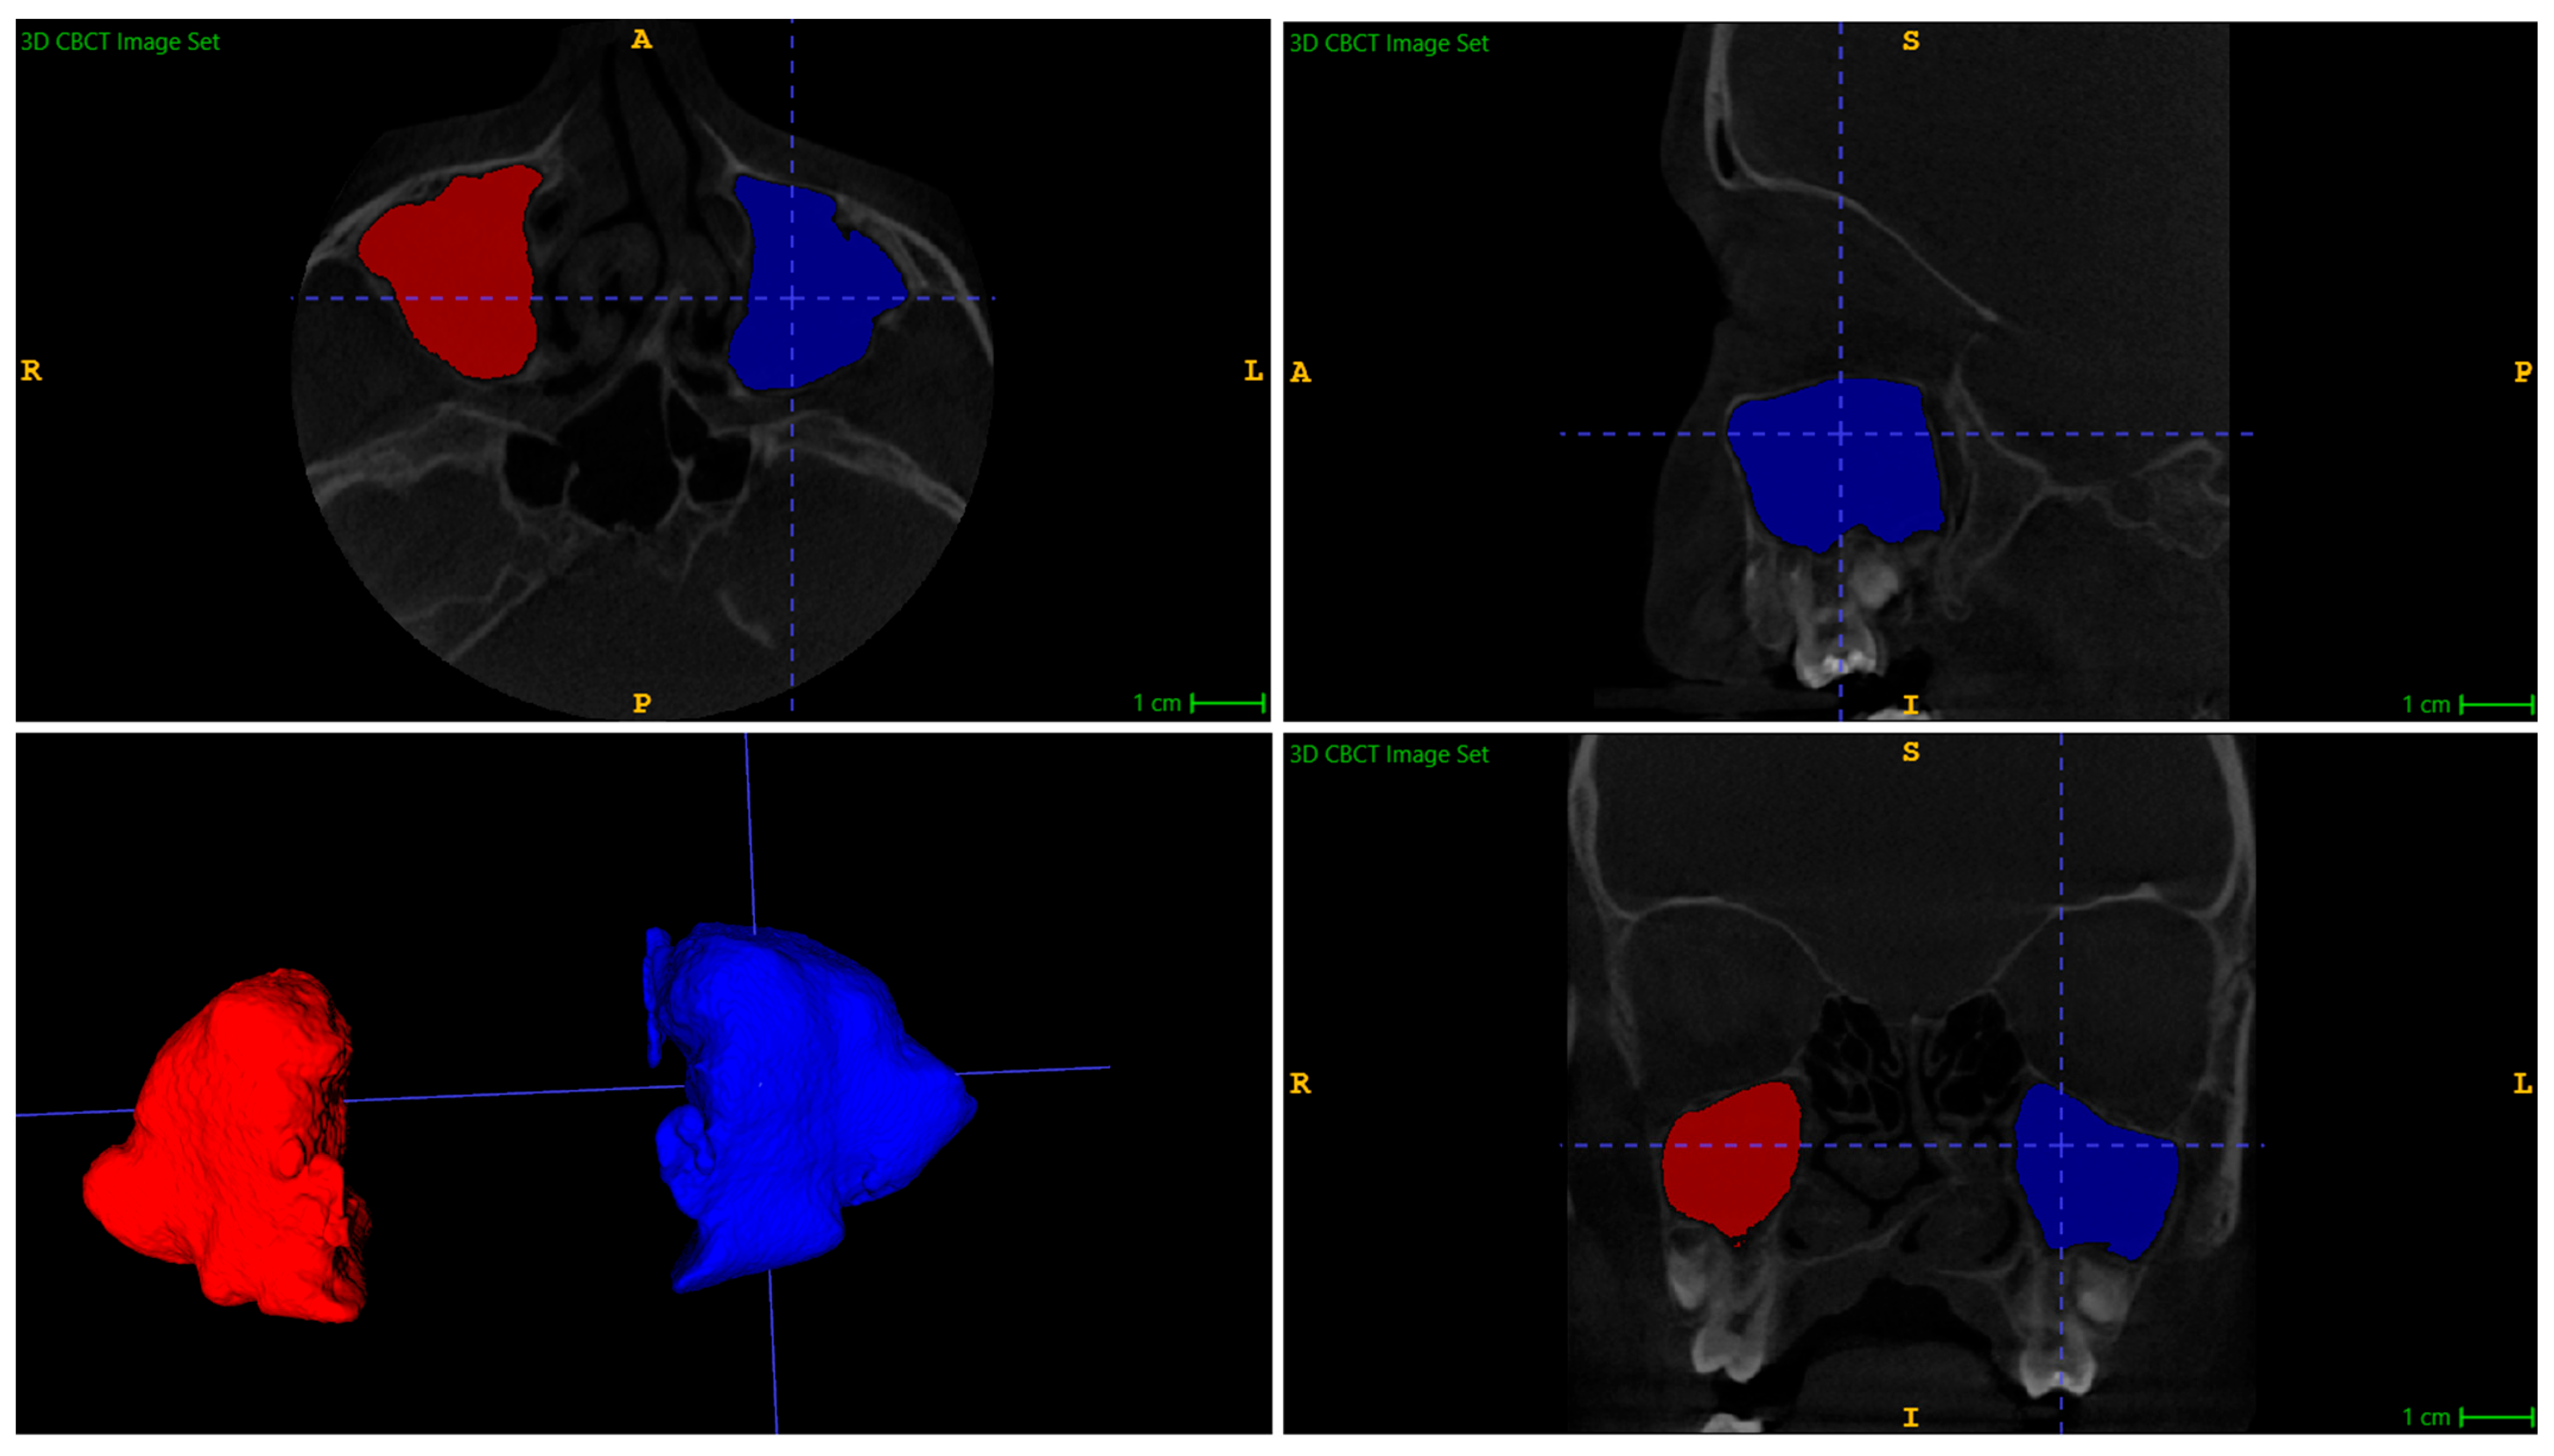

The volumes of the maxillary sinuses were measured before and after distraction using the ITK-SNAP version 4.2.2 (Philadelphia, PA, USA) 3D imaging software package. This software is a free, open-source segmentation tool used in neuroimaging and biomedical imaging research. The semi-automatic segmentation method was utilised to measure the maxillary sinus volumes, and the example of segmentation is shown in Figure 1. The surrounding tissues of all paranasal sinuses were removed using the Active Contour (Snake) Segmentation Mode, and pre-segmentation was performed using the Thresholding tool. Segmentation and measurement of the maxillary sinus were performed based on the bony contours of the sinuses. In cases with radiological features of chronic sinusitis, segmentation and measurement included the air-filled part of the sinus cavity, as well as any soft tissues within the skeletal boundaries of each sinus. The presence of soft tissues inside the cavity did not influence the anatomical volume or the reported measurements. Automatic software measurements of the sinus volumes (in cubic millimetres) were exported to a data table.

Figure 1. Maxillary sinus volume reconstruction in ITK-SNAP.